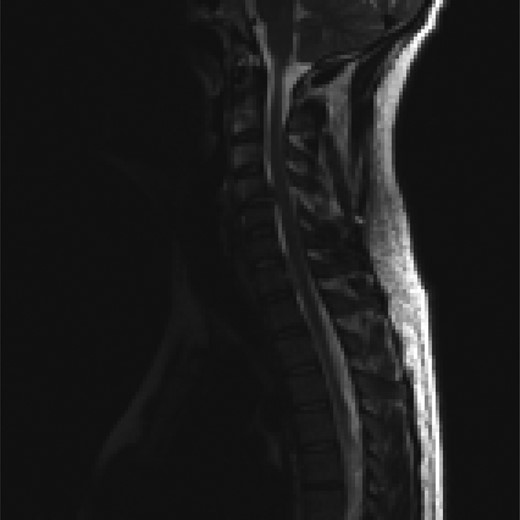

The MR of the C-Spine revealed C4/C5 subluxation (flexion–distraction injury) with total rupture of posterior ligamentous complex including PLL with acute traumatic disc herniation at C4/C5 level causing significant narrowing of the spinal canal at the level but no evidence of cord signal changes. Partial injury to Nuchal ligament with an acute injury to C6/C7 disc with posterior annular tear with disc extrusion, almost sequestration behind vertebral body of C7 towards left C7/T1 neural foramen, was also noted (Figs 3–5).

Sagittal T2-weighted MRI images showing a disc herniation at C4/5 and a non-contiguous disc extrusion at C/67 behind the vertebral body of C7.